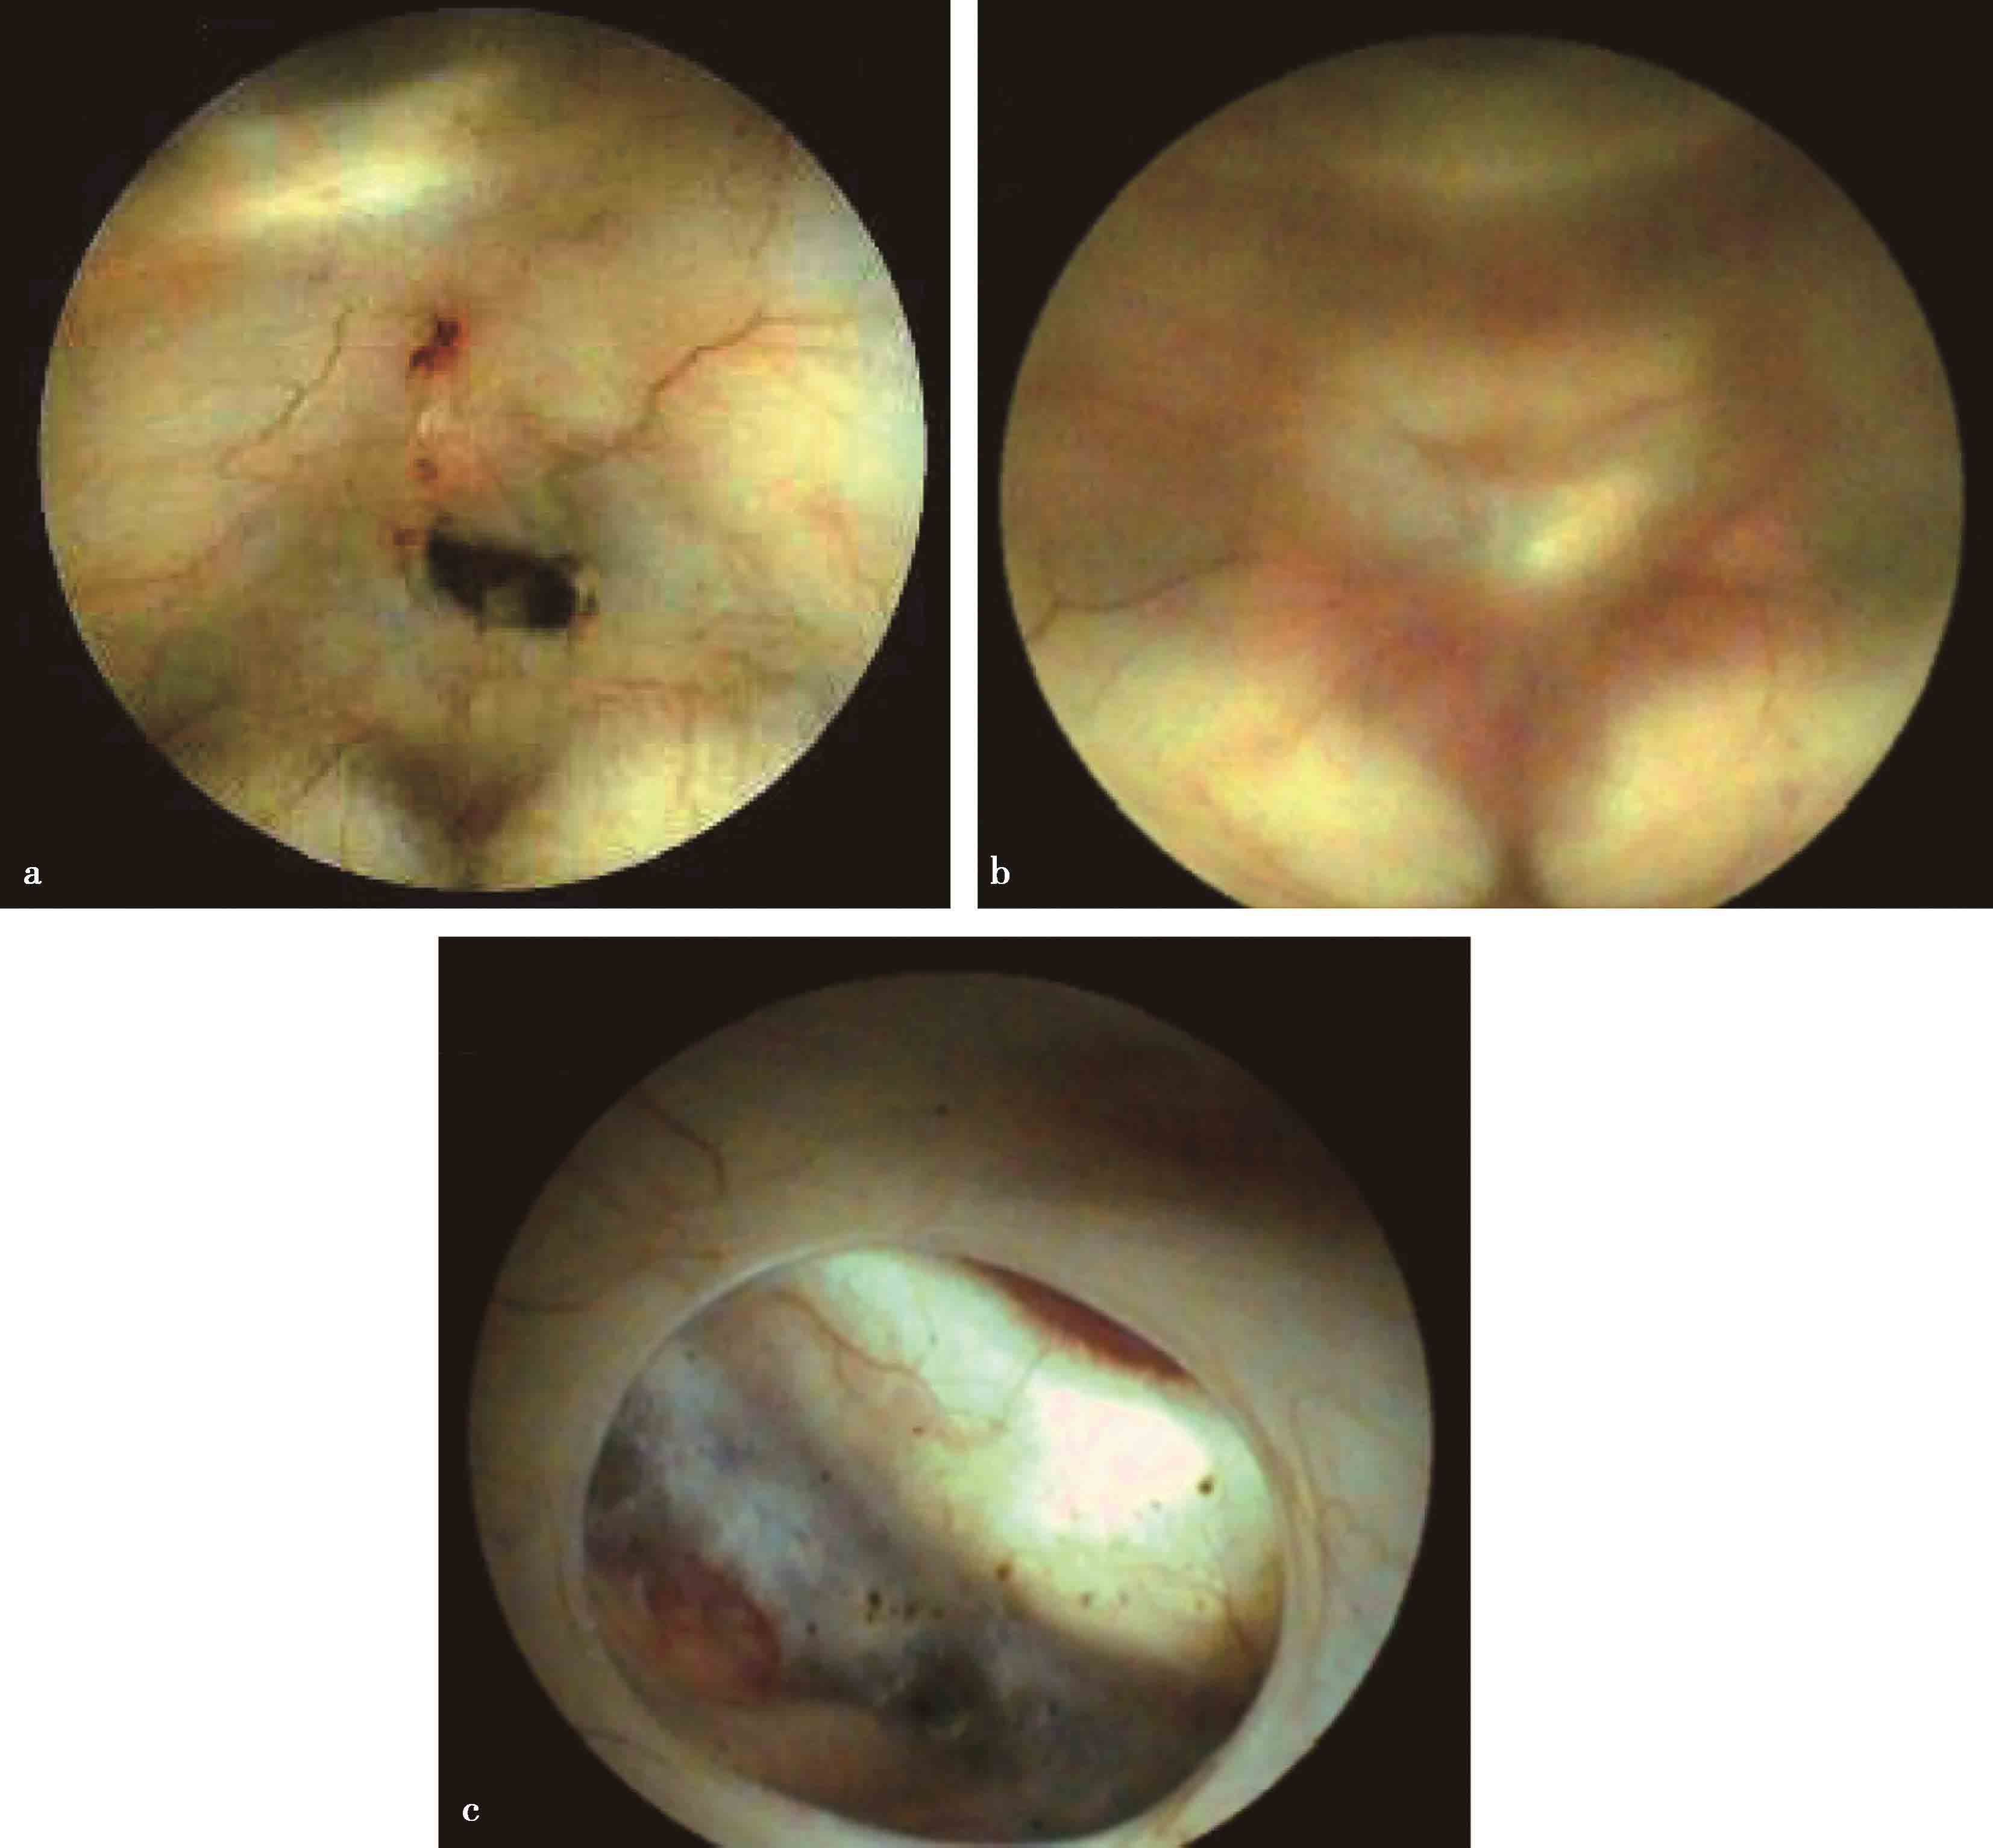

图3-1-2-9 内镜下脑室灌洗

a.出血后脑积水,侧脑室枕角遗留的陈旧性出血;b.脑室积脓

图3-1-2-10 脑室内多发分隔型复杂脑积水

a.MRI矢状位片示脑室内多发分隔;b.分流术后,CT显示脑室内多发分隔;c.脑室出血继发感染后,MRI显示脑室内多发分隔